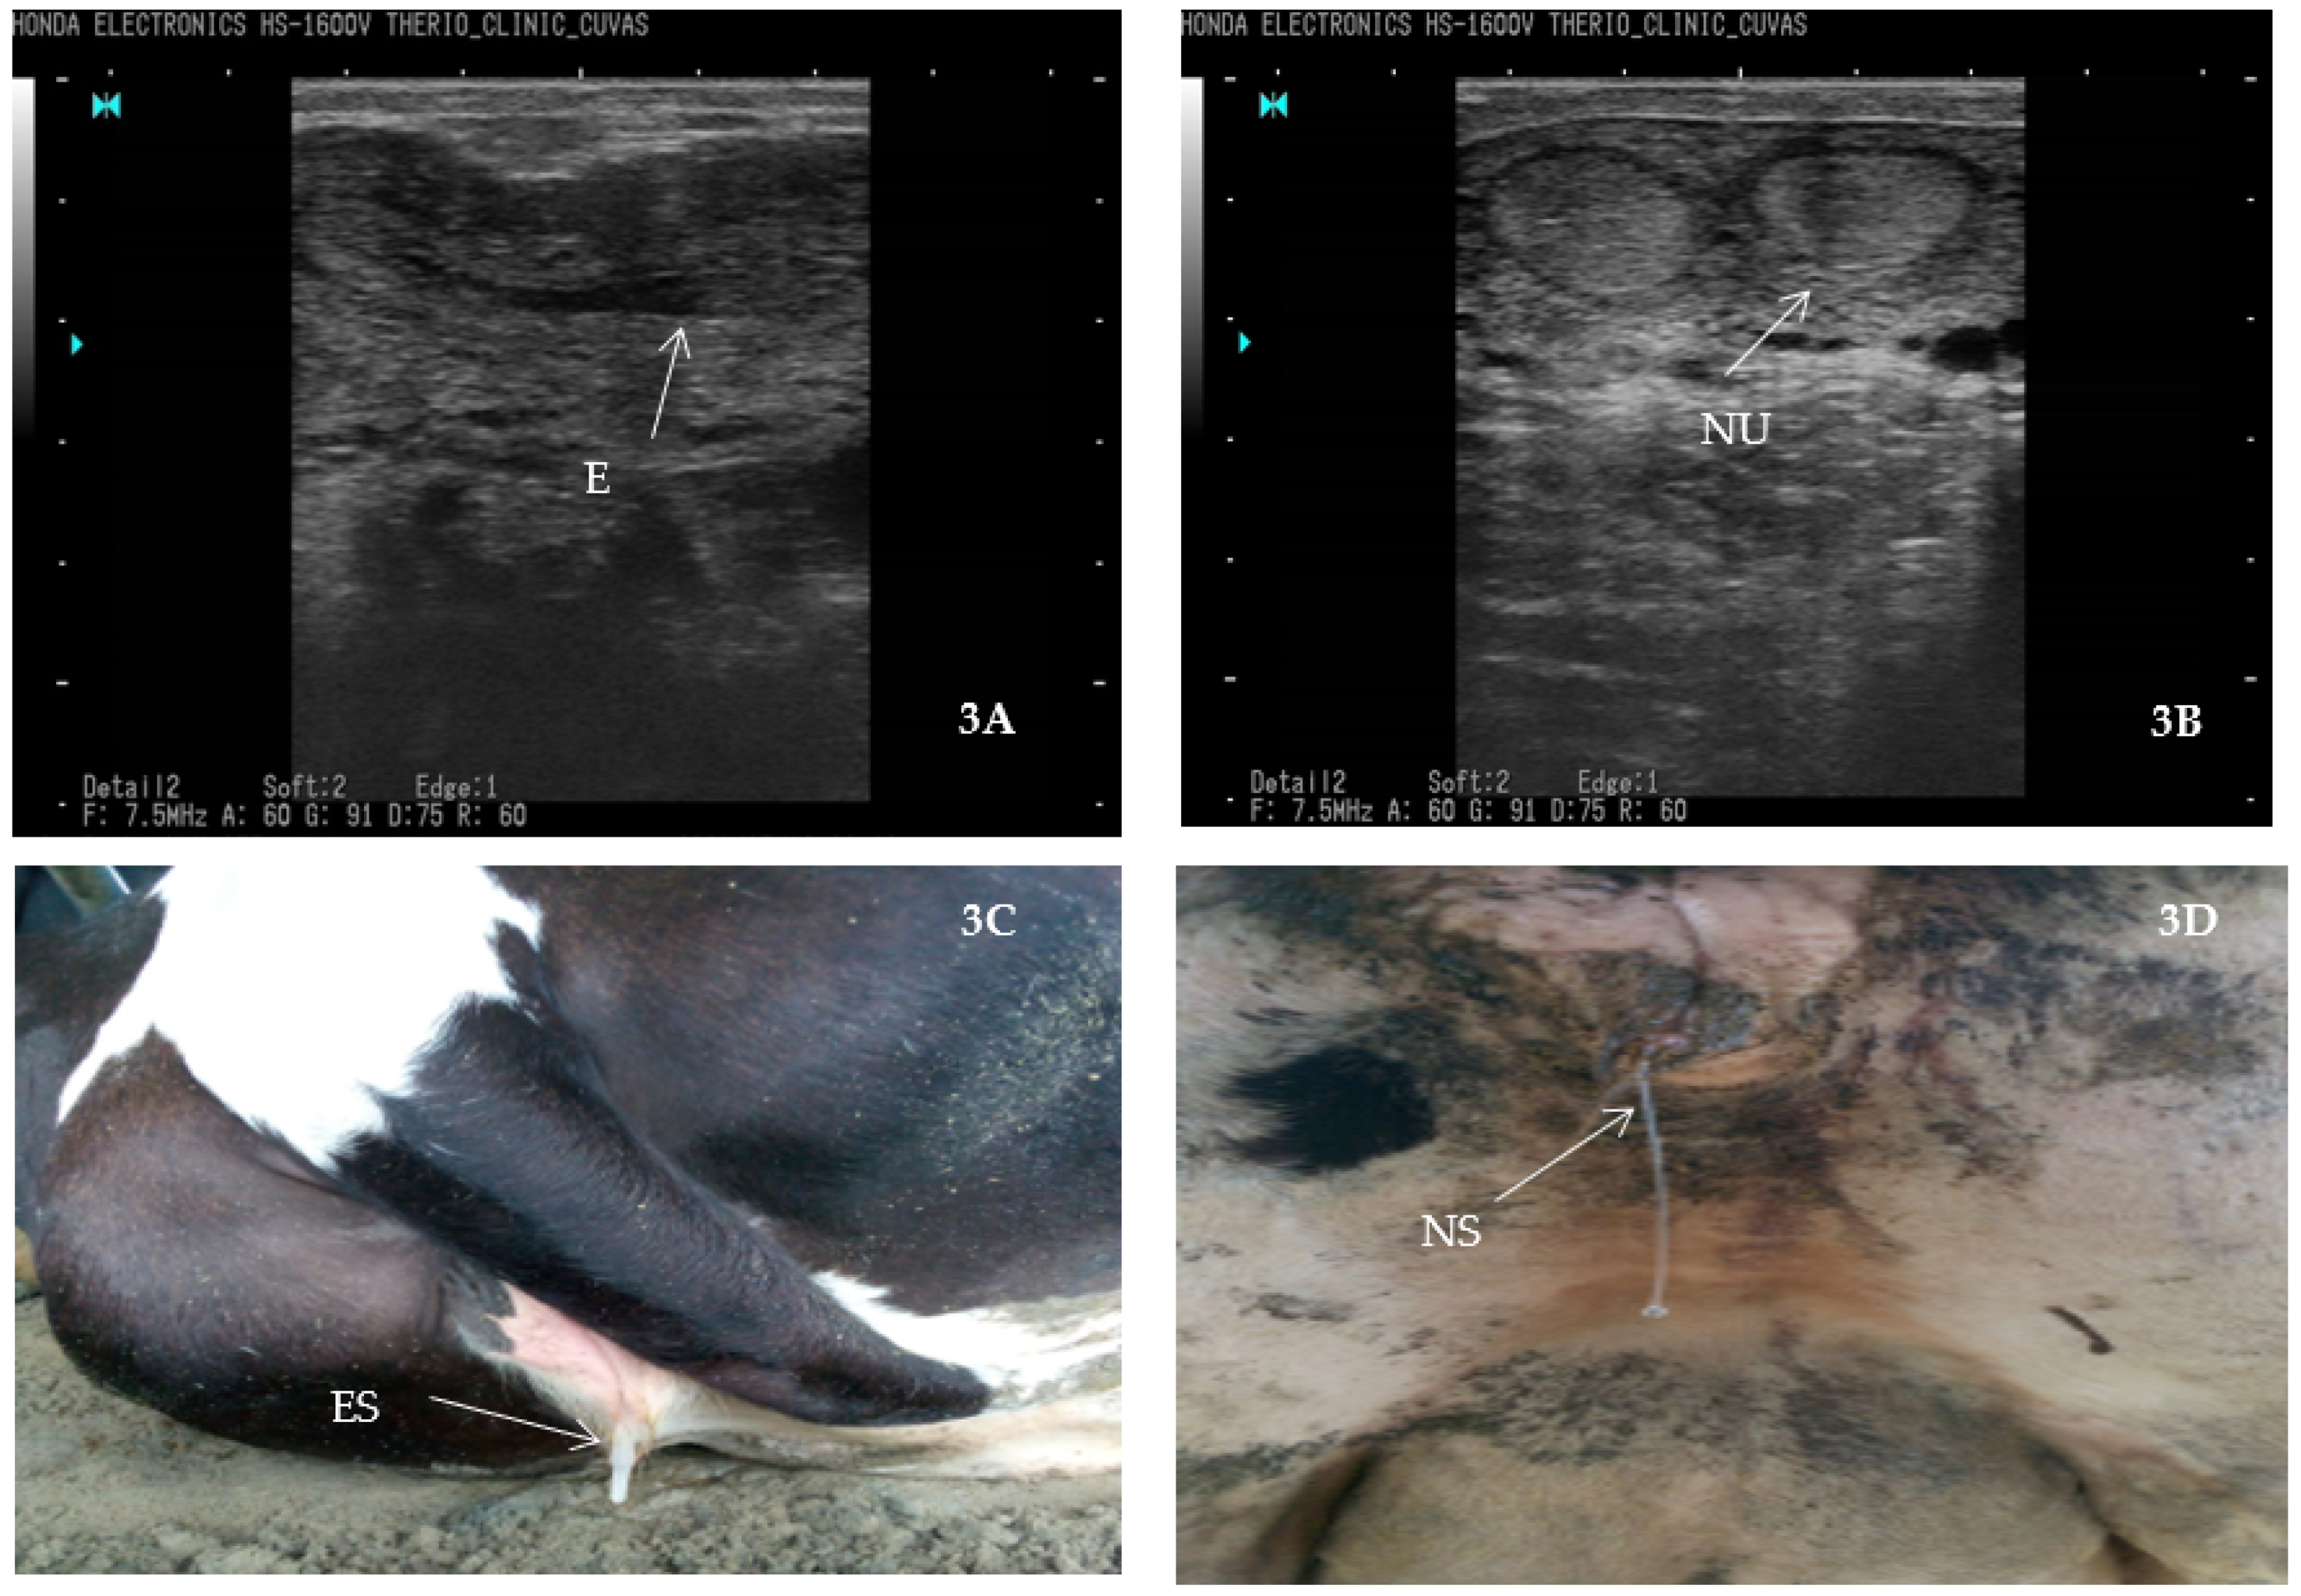

4.6.1. Tracking Bovine Endometritis

- Fissore, R.A.; Edmondson, A.J.; Pashen, R.L.; Bondurant, R.H. The use of ultrasonography for the study of the bovine reproductive tract. II. Non-pregnant, pregnant and pathological conditions of the uterus. Anim. Reprod. Sci. 1986, 12, 167–177. [Google Scholar] [CrossRef]

- Ihnatsenka, B.; Boezaart, A.P. Ultrasound: Basic understanding and learning the language. Int. J. Shoulder Surg. 2010, 4, 55. [Google Scholar]